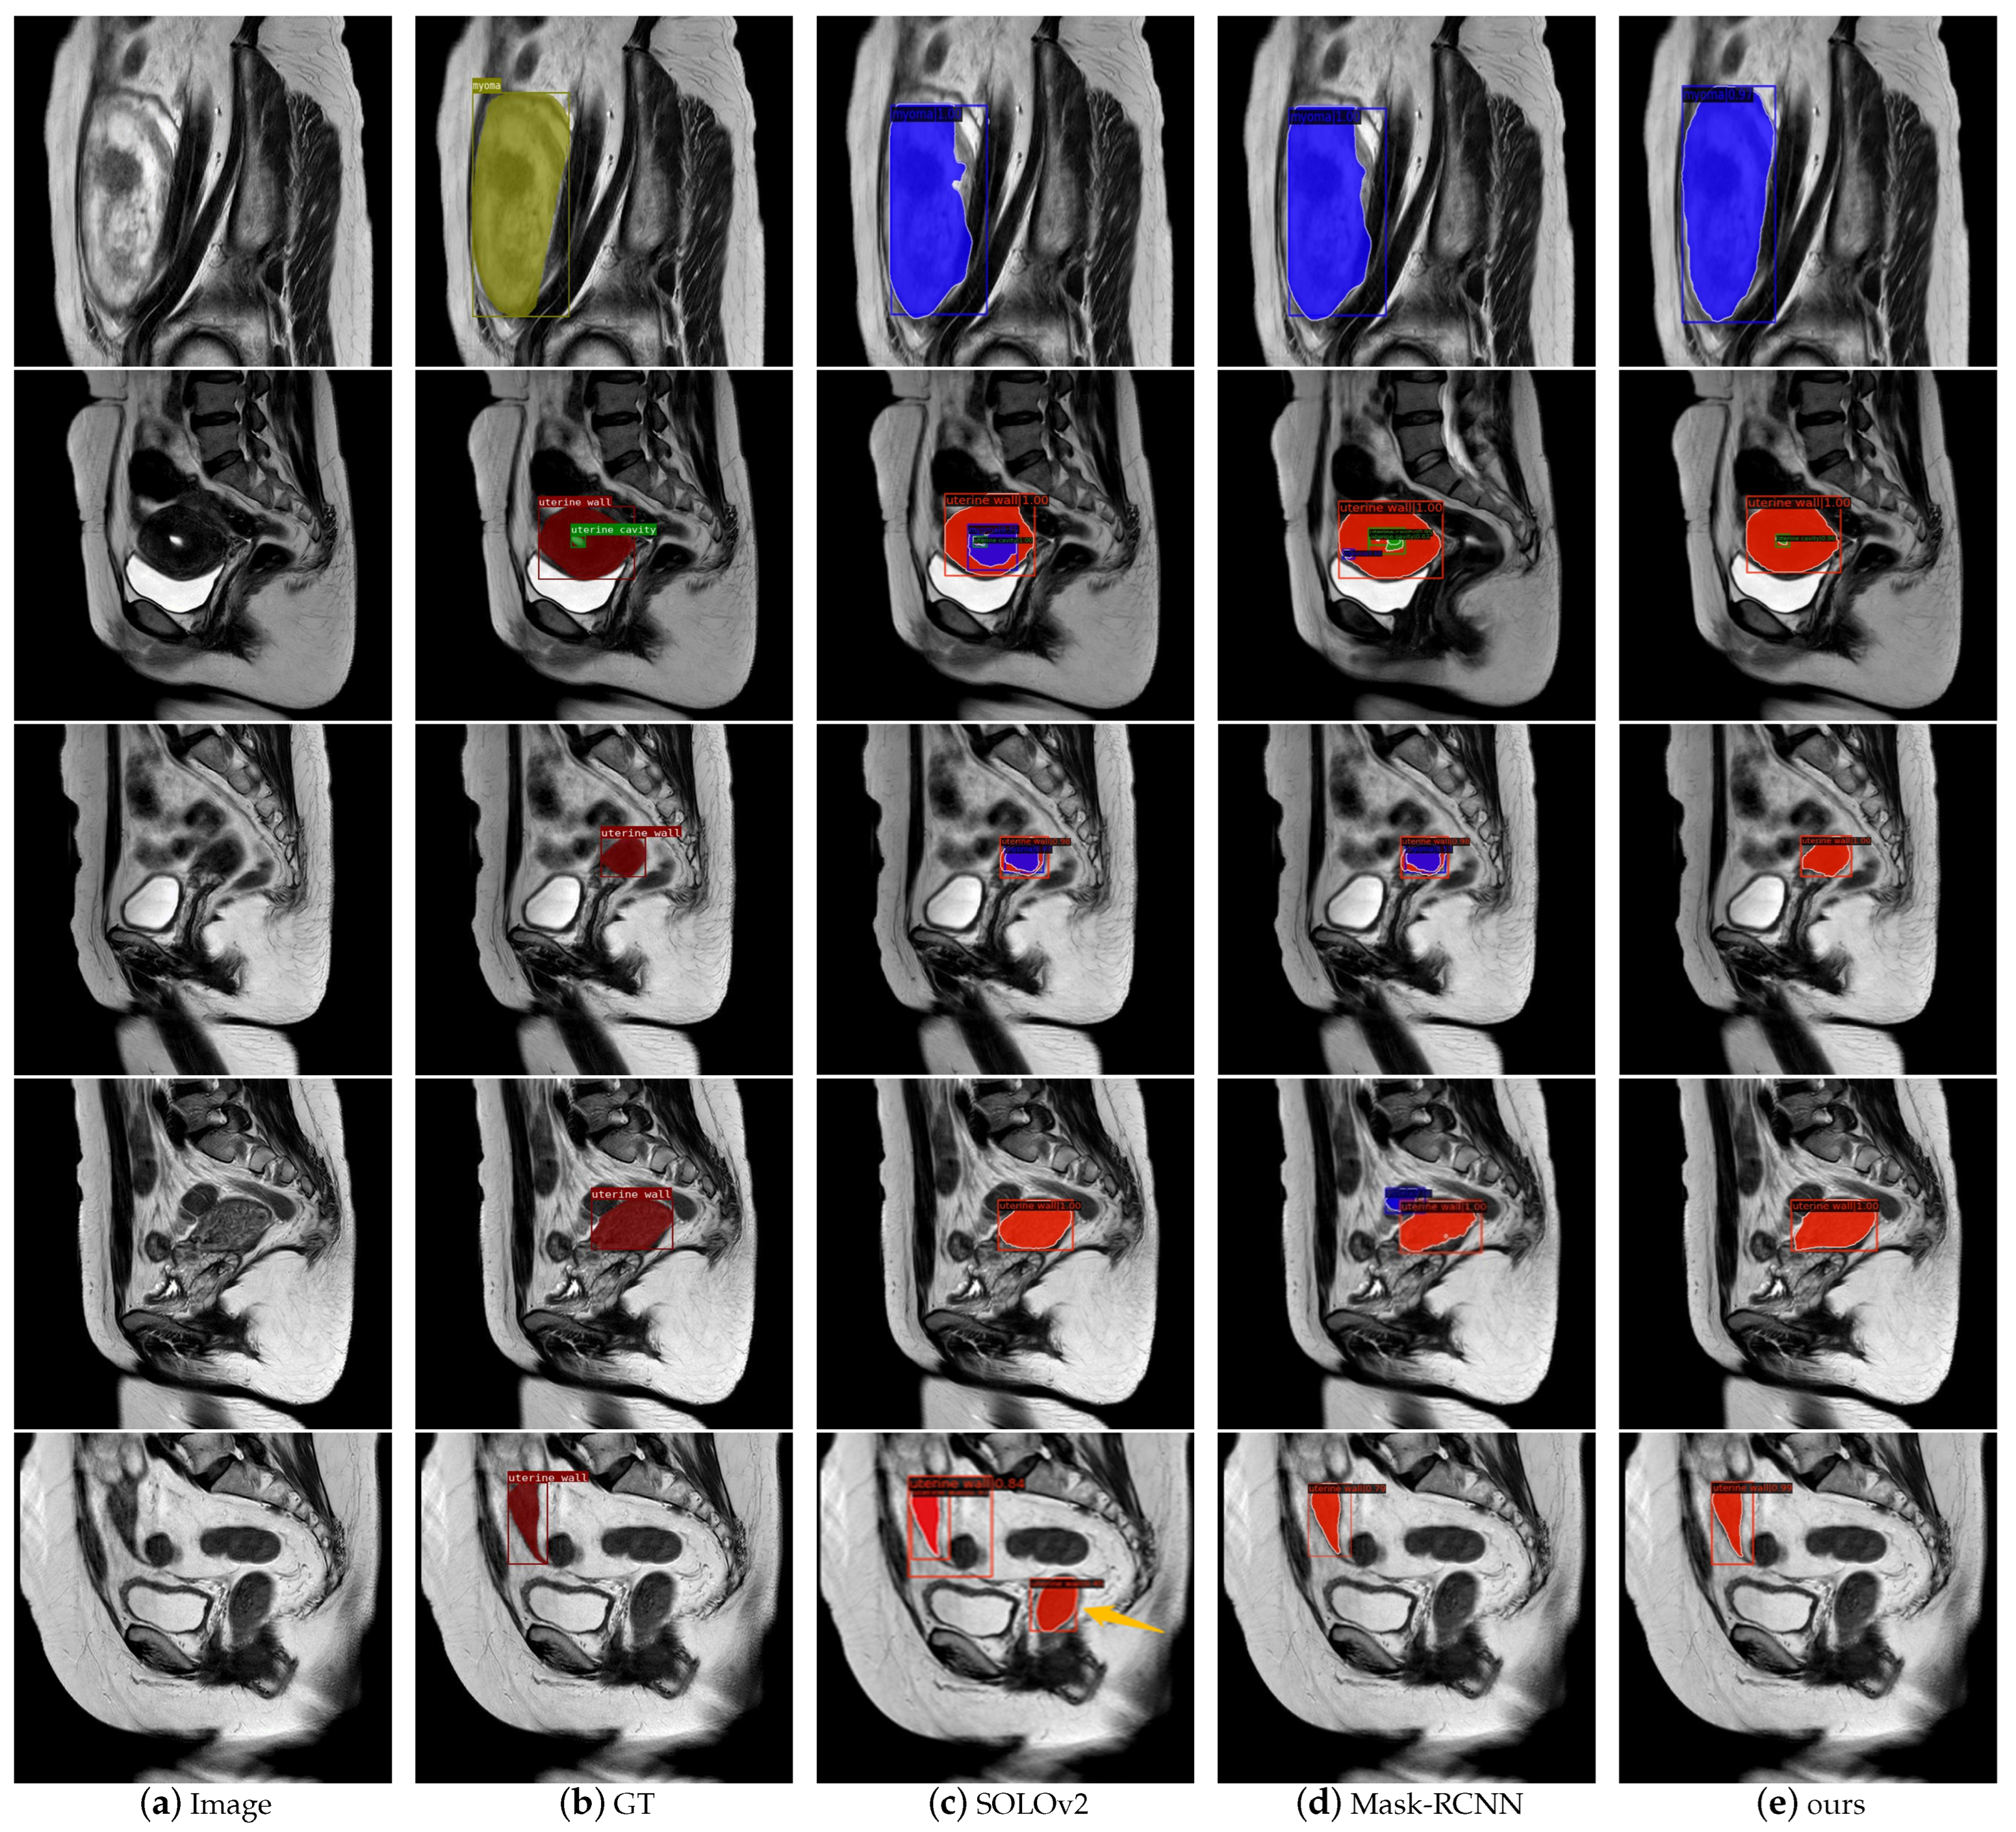

- We validated our approach with some excellent models and visualized its segmentation performance.

3.4. Comparison with Popular Models

4. Discussion